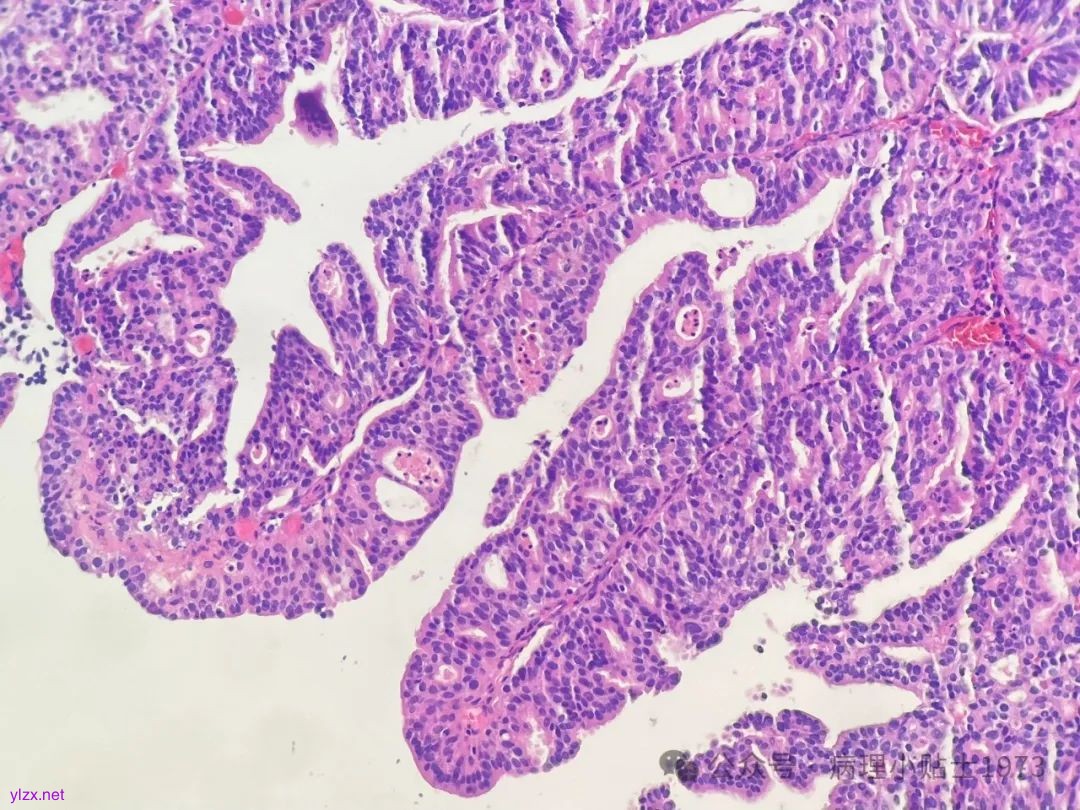

02 病例切片

诊断:非浸润性乳头状尿路上皮癌伴显著腺性分化

尿路上皮癌的诊断标准大家并不陌生,尿路上皮癌除了有很多组织学亚型,还可出现多种变异型(异向分化):包括伴鳞状分化、腺样分化、滋养细胞分化和苗勒型分化。

问题一:本病例出现了显著的腺性分化,不要误诊为单纯的腺癌。仔细寻找,仍然可以见到复层排列的经典尿路上皮癌成分。

有研究指出:伴腺样分化的尿路上皮肿瘤常是高级别,低级别尿路上皮增生性病变伴腺样分化常常不是肿瘤,可能是腺性膀胱炎或旺炽性腺性囊性膀胱炎。